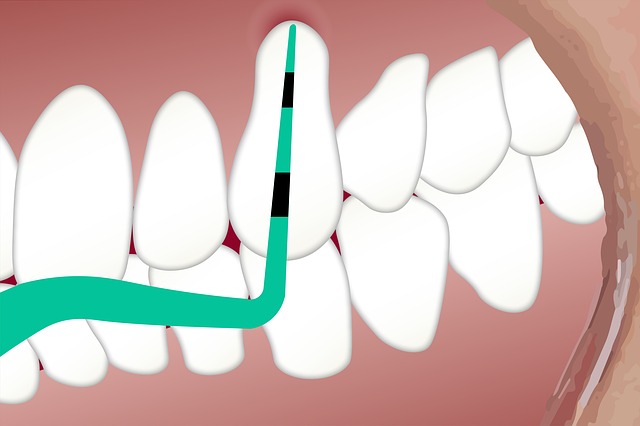

牙周病的治療步驟

第一階段 : 基本治療

醫師以工具深入到牙齦發炎的底部,徹底清潔牙齒表面與深部的髒東西,包括牙菌斑、牙結石及已被污染的齒質,這樣發炎的牙周組織才能緊貼牙根表面,恢復健康,牙周組織需經清除後觀察牙齦改善的狀況,再評估要不要手術的處理。